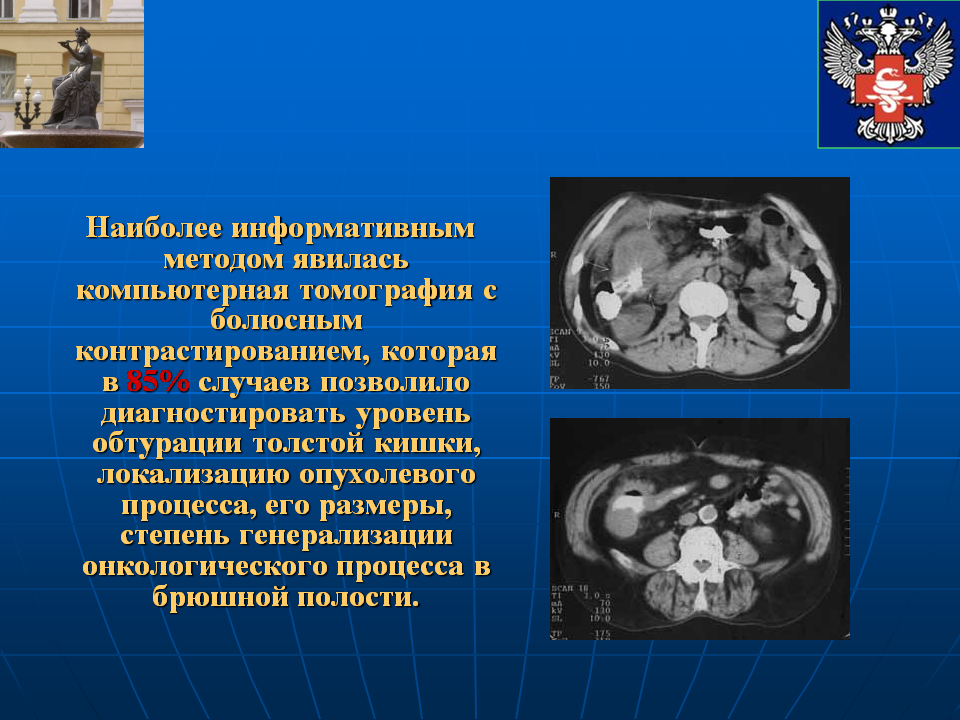

Гиповаскулярные метастазы печени кт. Опухоль желудка метастазирование. План обследования ободочной кишки. Диагноз опухоли ободочной кишки. Диагностические методы исследования ободочной кишки. Алгоритмы диагностики заболеваний толстой кишки.

План обследования ободочной кишки. Диагноз опухоли ободочной кишки. Диагностические методы исследования ободочной кишки. Алгоритмы диагностики заболеваний толстой кишки. Петрокливальная менингиома. Менингиома доброкачественная.

Диагностические критерии глиомы головного мозга. Особенности опухолей лобной доли. Клиника опухоли затылочной доли головного мозга. Симптомы, характерные для опухолей лобной доли. Компьютерная томография с болюсным контрастированием. Кт толстой кишки с контрастированием. Кт с болюсным контрастированием что это.

Компьютерная томография с болюсным контрастированием. Кт толстой кишки с контрастированием. Кт с болюсным контрастированием что это. Глиобластома мультиформная степень 4. Неоперабельная глиобластома головного мозга.. Глиобластома лобной доли мрт. Глиобластома злокачественная опухоль агрессивная.